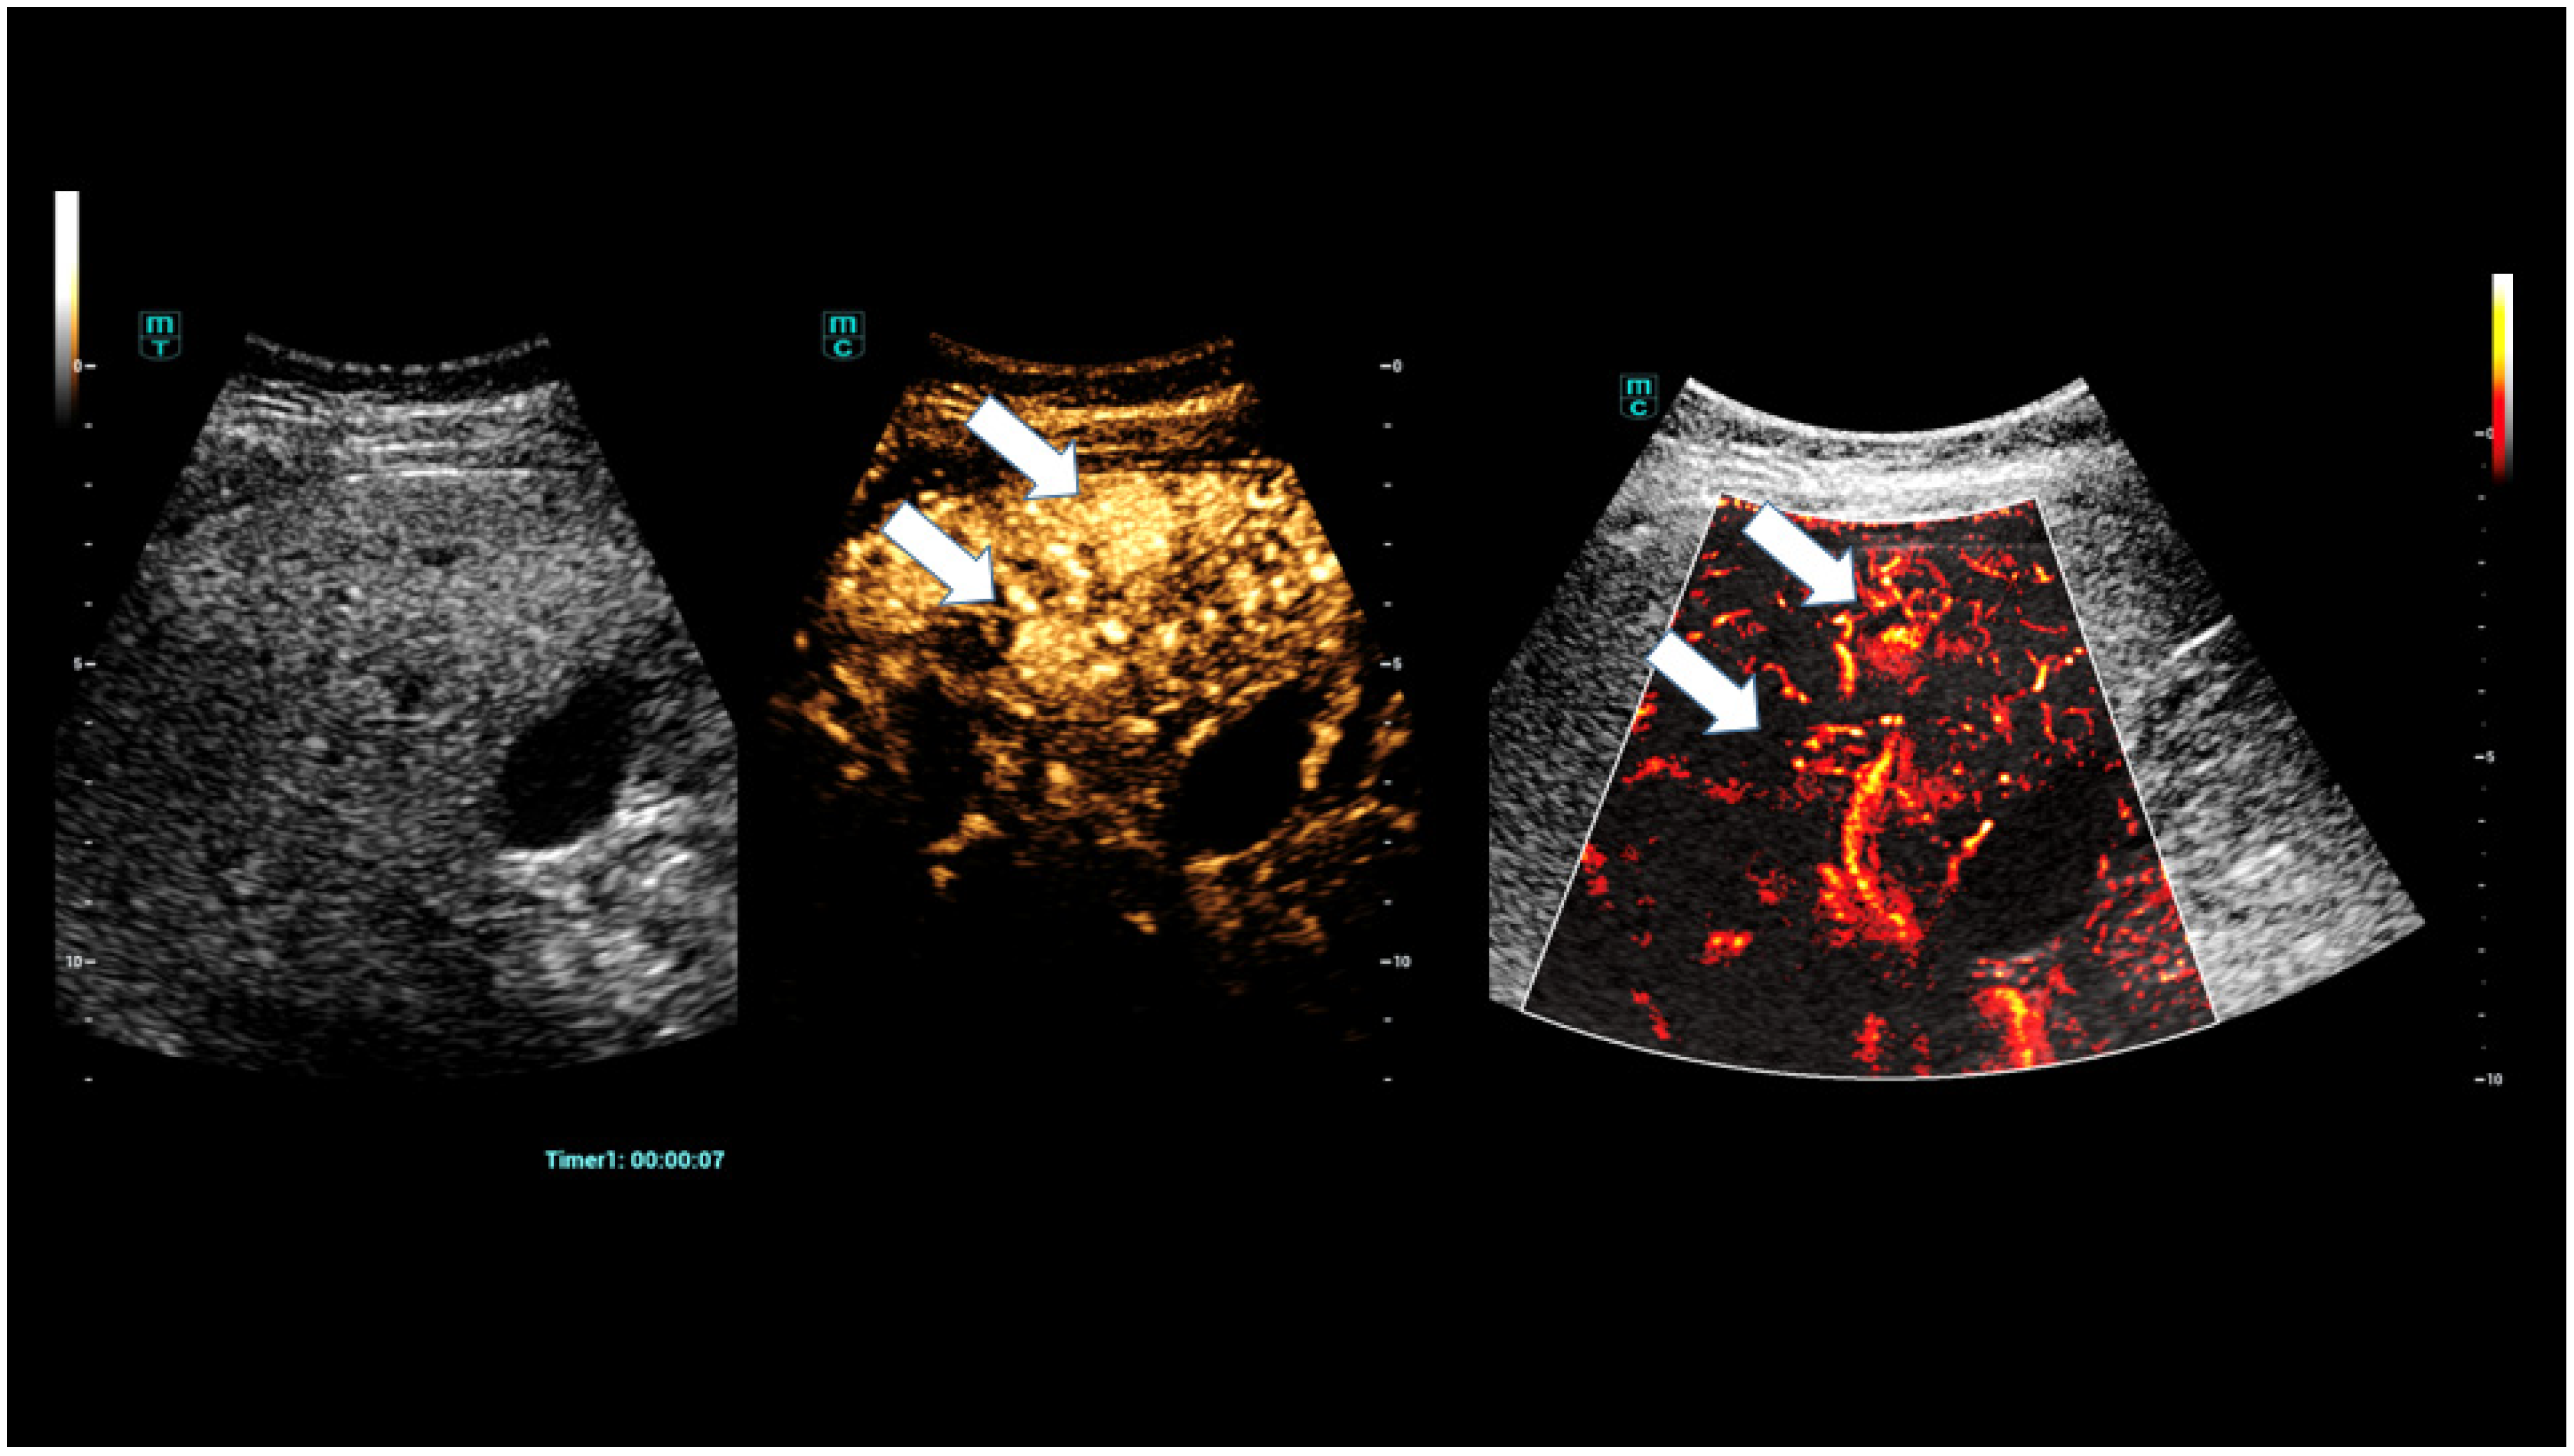

- Schelker, R.C.; Andorfer, K.; Putz, F.; Herr, W.; Jung, E.M. Identification of two distinct hereditary hemorrhagic telangiectasia patient subsets with different hepatic perfusion properties by combination of contrast-enhanced ultrasound (CEUS) with perfusion imaging quantification. PLoS ONE 2019, 14, e0215178. [Google Scholar] [CrossRef]

- Schelker, R.C.; Barreiros, A.P.; Hart, C.; Herr, W.; Jung, E.M. Macro- and microcirculation patterns of intrahepatic blood flow changes in patients with hereditary hemorrhagic telangiectasia. World J. Gastroenterol. 2017, 23, 486–495. [Google Scholar] [CrossRef]

- Möller, K.; Tscheu, T.; De Molo, C.; Serra, C.; Cui, X.W.; Dong, Y.; Hocke, M.; Lim, A.; Zadeh, E.S.; Görg, C.; et al. Comments and illustrations of the WFUMB CEUS liver guidelines: Rare congenital vascular pathology. Med. Ultrason. 2022, 24, 461–472. [Google Scholar] [CrossRef]